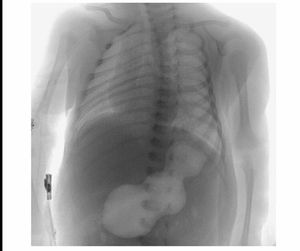

Hypertrophic pyloric stenosis, its preference to male gender is quite intriguing. Ddx: obstruction by a mass lesion(given the age).

Hypertrophic pyloric stenosis ;UGI Fluoroscopy show :distended stomach ,Caterpillar sign,string sign due to enlarged pylorus with narrow Lumen ,beak sign